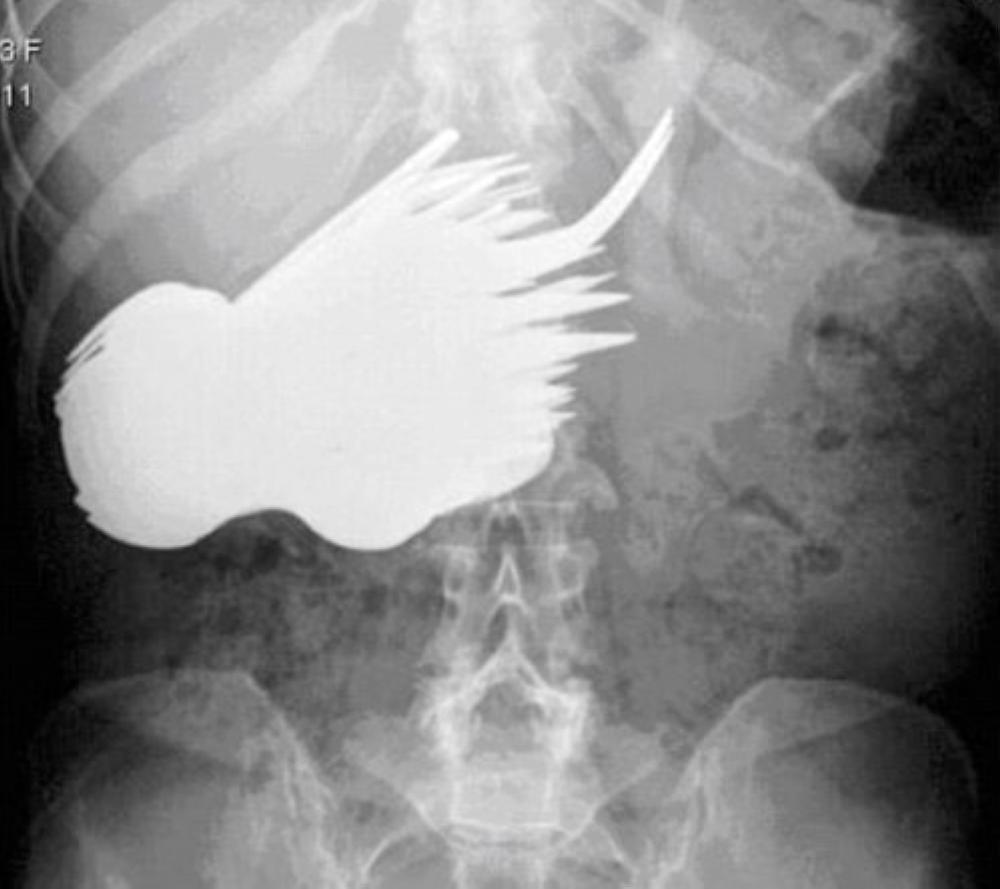

لم يعد مفاجئا أن يكتشف الأطباء مقصا جراحيا أو ملقاطا طبيا أو حتى شريطا لاصقا في بطن أحد المرضى، بعد خضوعه لعملية جراحية، إلا أن الغريب أن يعثر الأطباء على 78 شوكة وسكينة وملعقة في معدة امرأة تبلغ من العمر 52 عاما، حين أحضرها أحد أبنائها محمولة إلى طوارئ أحد مستشفيات هولندا. تشكو آلاما حادة في بطنها بشكل عام. وبعد إجراء التحاليل والأشعات اللازمة، فوجئ الأطباء بوجود عدد كبير من القطع المعدنية، لم يتمكنوا من تشخيصها، إلا بعد إخضاع المرأة لجراحة عاجلة، ليكتشفوا في غرفة العمليات وجود هذا العدد الكبير من أدوات المطبخ، فيما استغرق إجراء العملية أكثر من 7 ساعات لانتشال الشوك والملاعق والسكاكين.